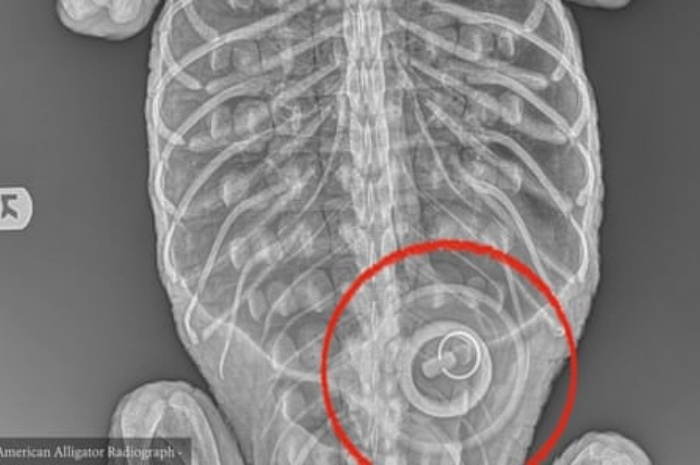

<p>Keterangan Foto: hasil pemeriksaan tubuh buaya di AS yang terdapay sumbatan di tubuhnya, (Foto:/Twitter/Wildlife Conservation Society (WCS)</p>

Menurut gambar radiografi dari Kebun Binatang Bronx, tempat Godzilla menerima perawatan, ada benda yang tersangkut di bagian kanan perutnya, sumbat bak mandi selebar 4 inci, kata WCS dalam pernyataannya.